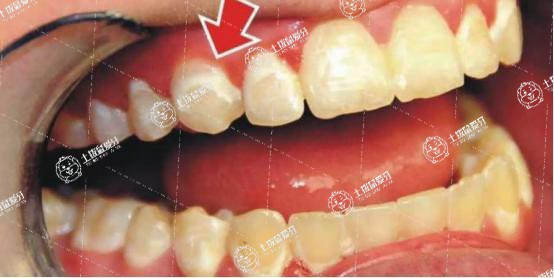

正畸牙齒時(shí)固定矯治器的托槽粘接的太靠近牙齦組織或調(diào)整加力時(shí)力量過大、由于戴矯治器后口腔衛(wèi)生不良引起的牙齦炎等,都可以造成牙齦腫脹。

如果是由于托槽粘接的太靠近牙齦組織刺激牙齦腫脹,需要重新粘接托槽。如果是由于調(diào)整力量時(shí)過大引起牙齦組織腫脹,可以通過減小調(diào)整力量或延長調(diào)整力量的時(shí)間來改善。